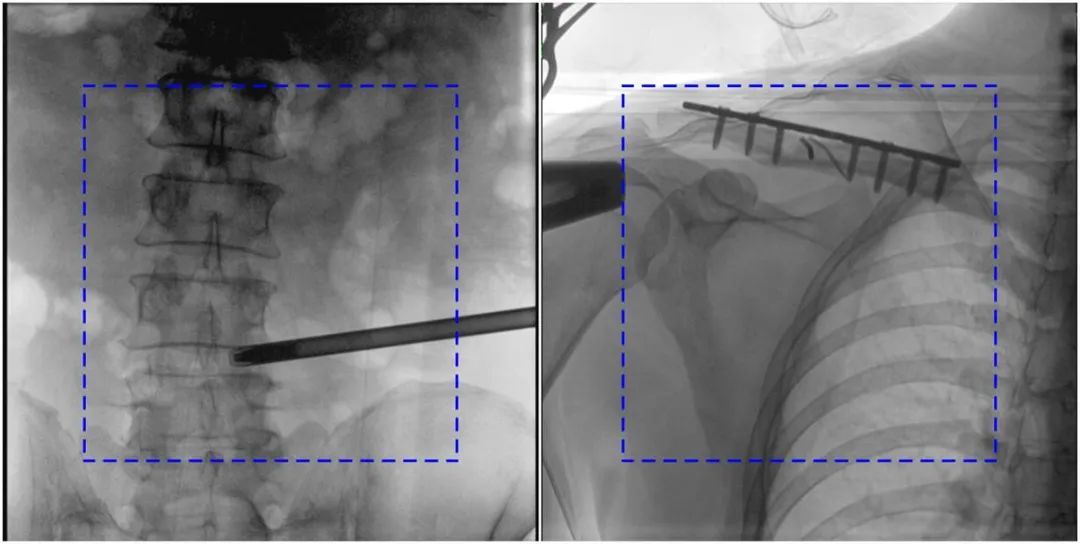

PLX119C臨床圖像與傳統(tǒng)圖像對(duì)比

注:藍(lán)色虛線內(nèi)為傳統(tǒng)21CM×21CM平板的成像區(qū)域。

在進(jìn)行髓內(nèi)釘內(nèi)固定術(shù)時(shí),醫(yī)生需要同時(shí)觀察到入釘點(diǎn)和骨折部位的情況,普愛醫(yī)療大平板一體式C形臂采用30CM×30CM的平板探測器,能夠呈現(xiàn)更廣闊的成像面積,滿足大部分長骨髓內(nèi)釘內(nèi)固定術(shù)的攝片需求。